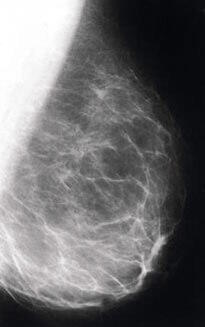

Stephen Cherniske : Je suis d'accord. Mais elles réfutent certainement votre diatribe selon laquelle la DHEA pourrait provoquer le cancer du sein. Il n'y a aucune preuve indiquant que la DHEA augmente le risque de cancer du sein. En fait, une étude publiée dans le prestigieux journal The Lancet a montré une remarquable corrélation entre de faibles niveaux de DHEA et le risque de cancer du sein27.